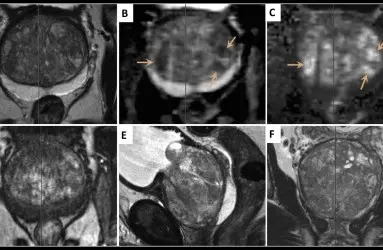

Tedaviler

Üroloji Uzmanı